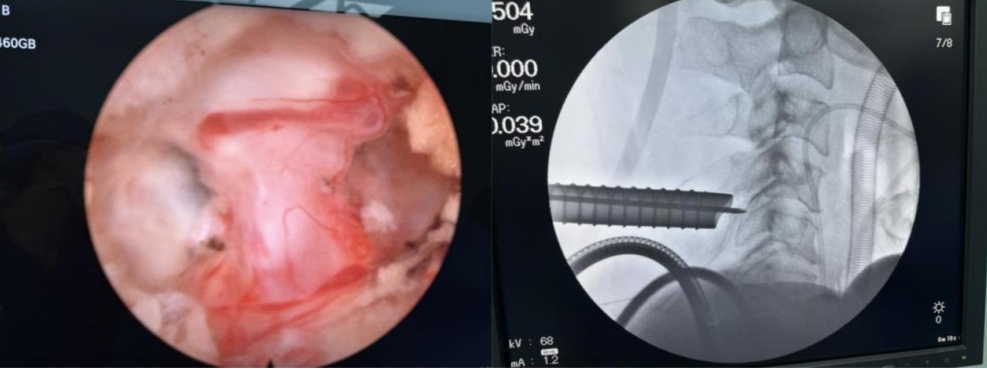

手术过程顺利,出血不到20ml。术后效果立竿见影,患者困扰多时的颈肩痛及右上肢放射痛、麻木等症状全部消失。

“Keyhole”意为“钥匙孔”。颈椎Keyhole手术,是脊柱内镜技术的一种形象称呼。医生通过一个微小的切口,置入高清内镜,在椎板上建立一个仅如钥匙孔大小的操作通道,精准地摘除突出的髓核,松解受压迫的神经根,从根本上解除病痛。